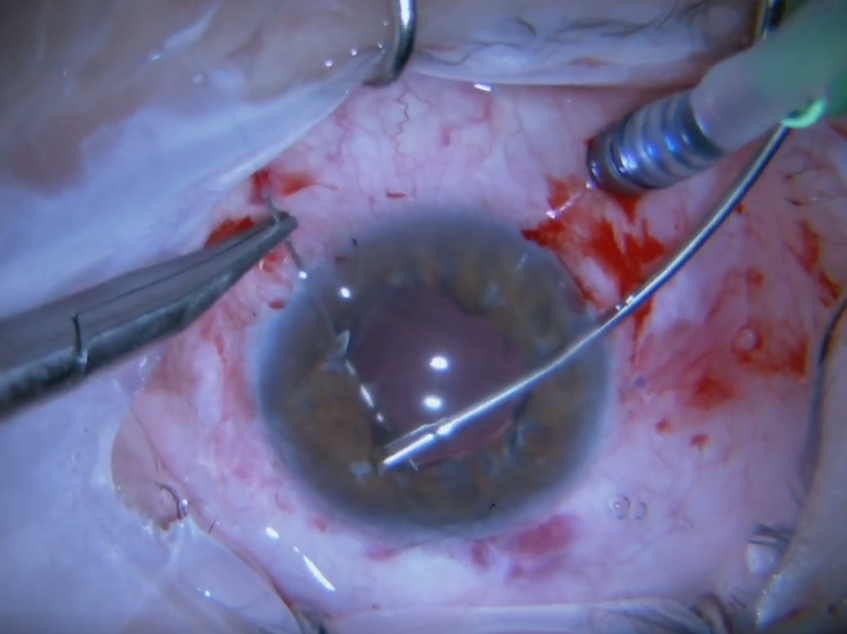

Retina dekolmanı cerrahisi sırasında perflorokarbon sıvı uygulaması esnasında ge ...